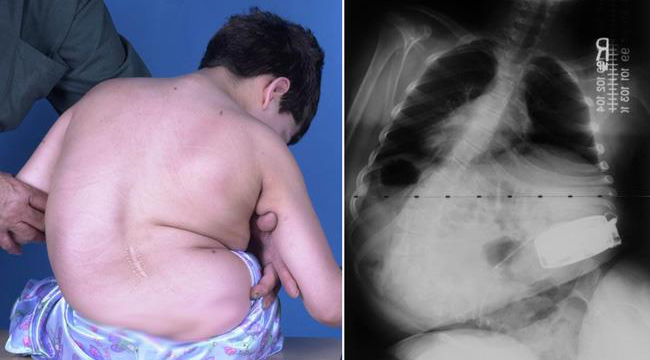

يعاني بعض الأطفال والمراهقين من اعوجاج العمود الفقري العصبي العضلي، وهو نوع معقد وخطير من الانحناءات يحدث نتيجة أمراض تصيب الجهاز العصبي أو العضلي، مثل الشلل الدماغي، ضمور العضلات الشوكي، أو إصابات الحبل الشوكي. هذا الانحناء لا يقتصر على تغيير شكل الظهر فقط، بل غالبًا ما يؤثر على الوظائف التنفسية، الحركة، وجودة الحياة اليومية. تتطور هذه الحالة تدريجيًا إذا لم يتم التدخل الطبي المبكر، مما يجعل المتابعة المستمرة أمرًا حيويًا للحفاظ على صحة الطفل وتحسين قدراته الحركية.

اعوجاج العمود الفقري العصبي العضلي هو انحناء غير طبيعي للعمود الفقري يحدث بسبب اضطراب في العضلات أو الأعصاب التي تدعم العمود الفقري. عندما تكون العضلات ضعيفة أو غير متوازنة، يفقد العمود الفقري ثباته الطبيعي، ويبدأ بالانحناء تدريجيًا. غالبًا ما يترافق هذا النوع مع أمراض مزمنة مثل:

هذا النوع من الاعوجاج يختلف عن اعوجاج المراهقين مجهول السبب في سرعة تطوره وتأثيره على الوظائف الحيوية، خصوصًا الجهاز التنفسي والحركة اليومية.

كيف يتم تشخيص اعوجاج العمود الفقري العصبي العضلي؟

يعتمد التشخيص على مجموعة من الفحوصات الطبية:

الفحص السريري لتقييم شكل الظهر والتوازن العضلي

الأشعة السينية لتحديد درجة الانحناء وزاويته

فحوصات الرئة لمعرفة مدى تأثير الانحناء على التنفس